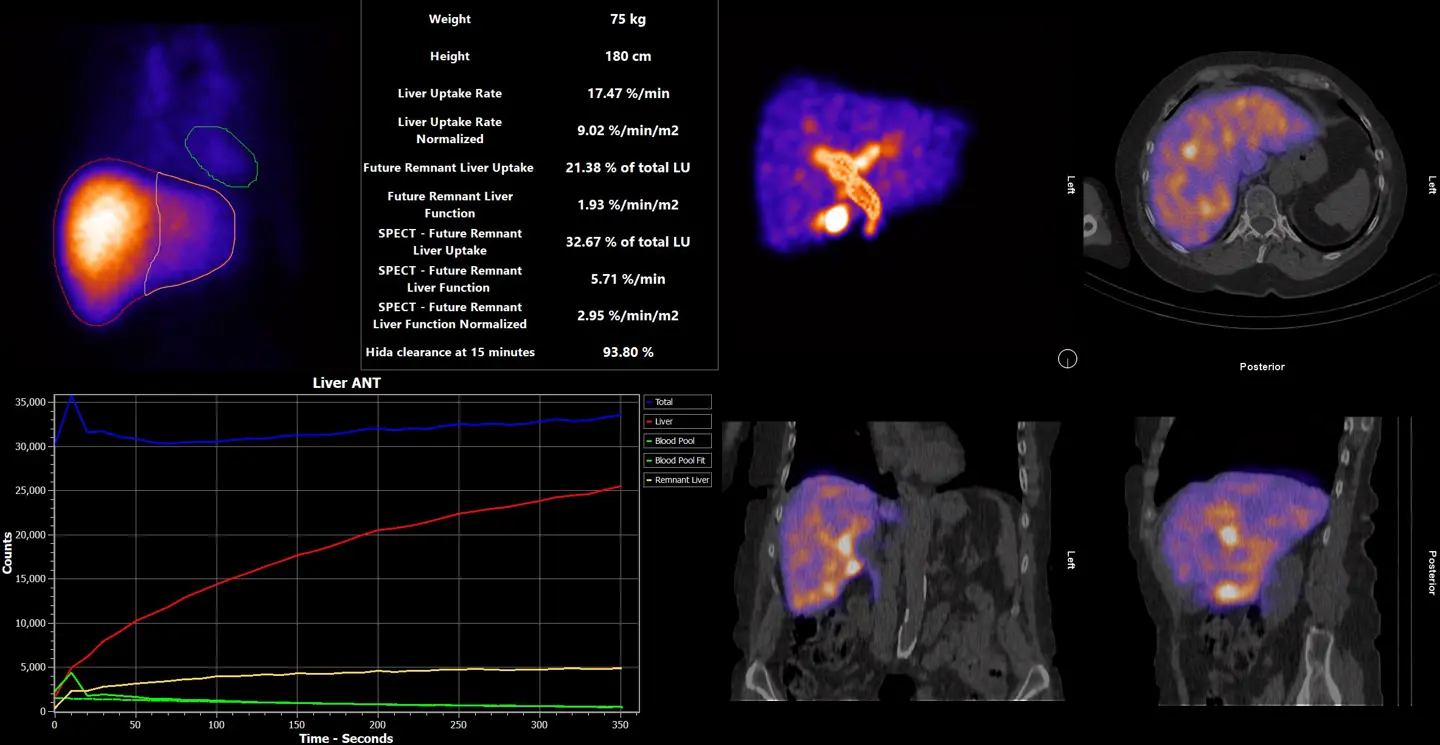

Hermia software allows you to obtain quantitative results to assess post-surgical future remnant liver function in minutes.

Hermia software analysis allows you to obtain quantitative results to assess post-surgical future remnant liver function in minutes – regardless of the camera vendor.

Obtain quantitative results for post-surgical future remnant liver function in minutes

Confident surgical planning

Hepatobiliary imaging and software analysis to assess Future Remnant Liver Function